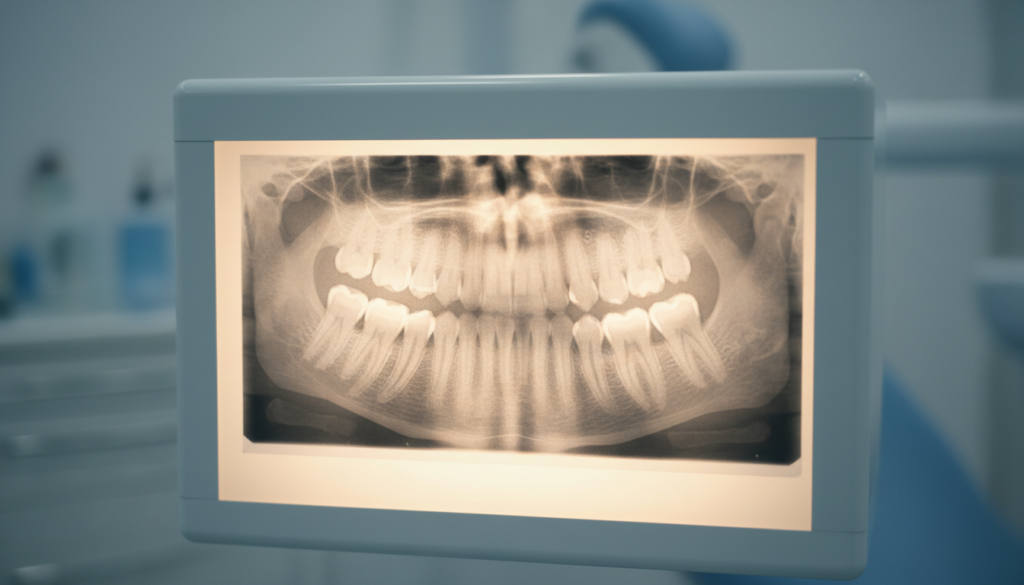

パノラマレントゲン

お口全体を1枚で撮影できる装置です。

全体的な歯の状態、顎の骨の状態、親知らずの位置などを把握するのに適しています。初診時に全体像を確認する目的で使われることが多いです。

レントゲン撮影をすることで、根管の本数・長さ・曲がり具合、そして感染がどこまで広がっているかを確認できます。特に奥歯は根が複数あり、重なって見えることもあるため、角度を変えて複数枚撮影することが重要です。

1枚だけのレントゲンでは、本来2本ある根管が1本に見えてしまう場合があります。見落としや診断ミスを防ぐために、正面と斜めの2方向から撮影することが、精密な根管治療の基本とされています。